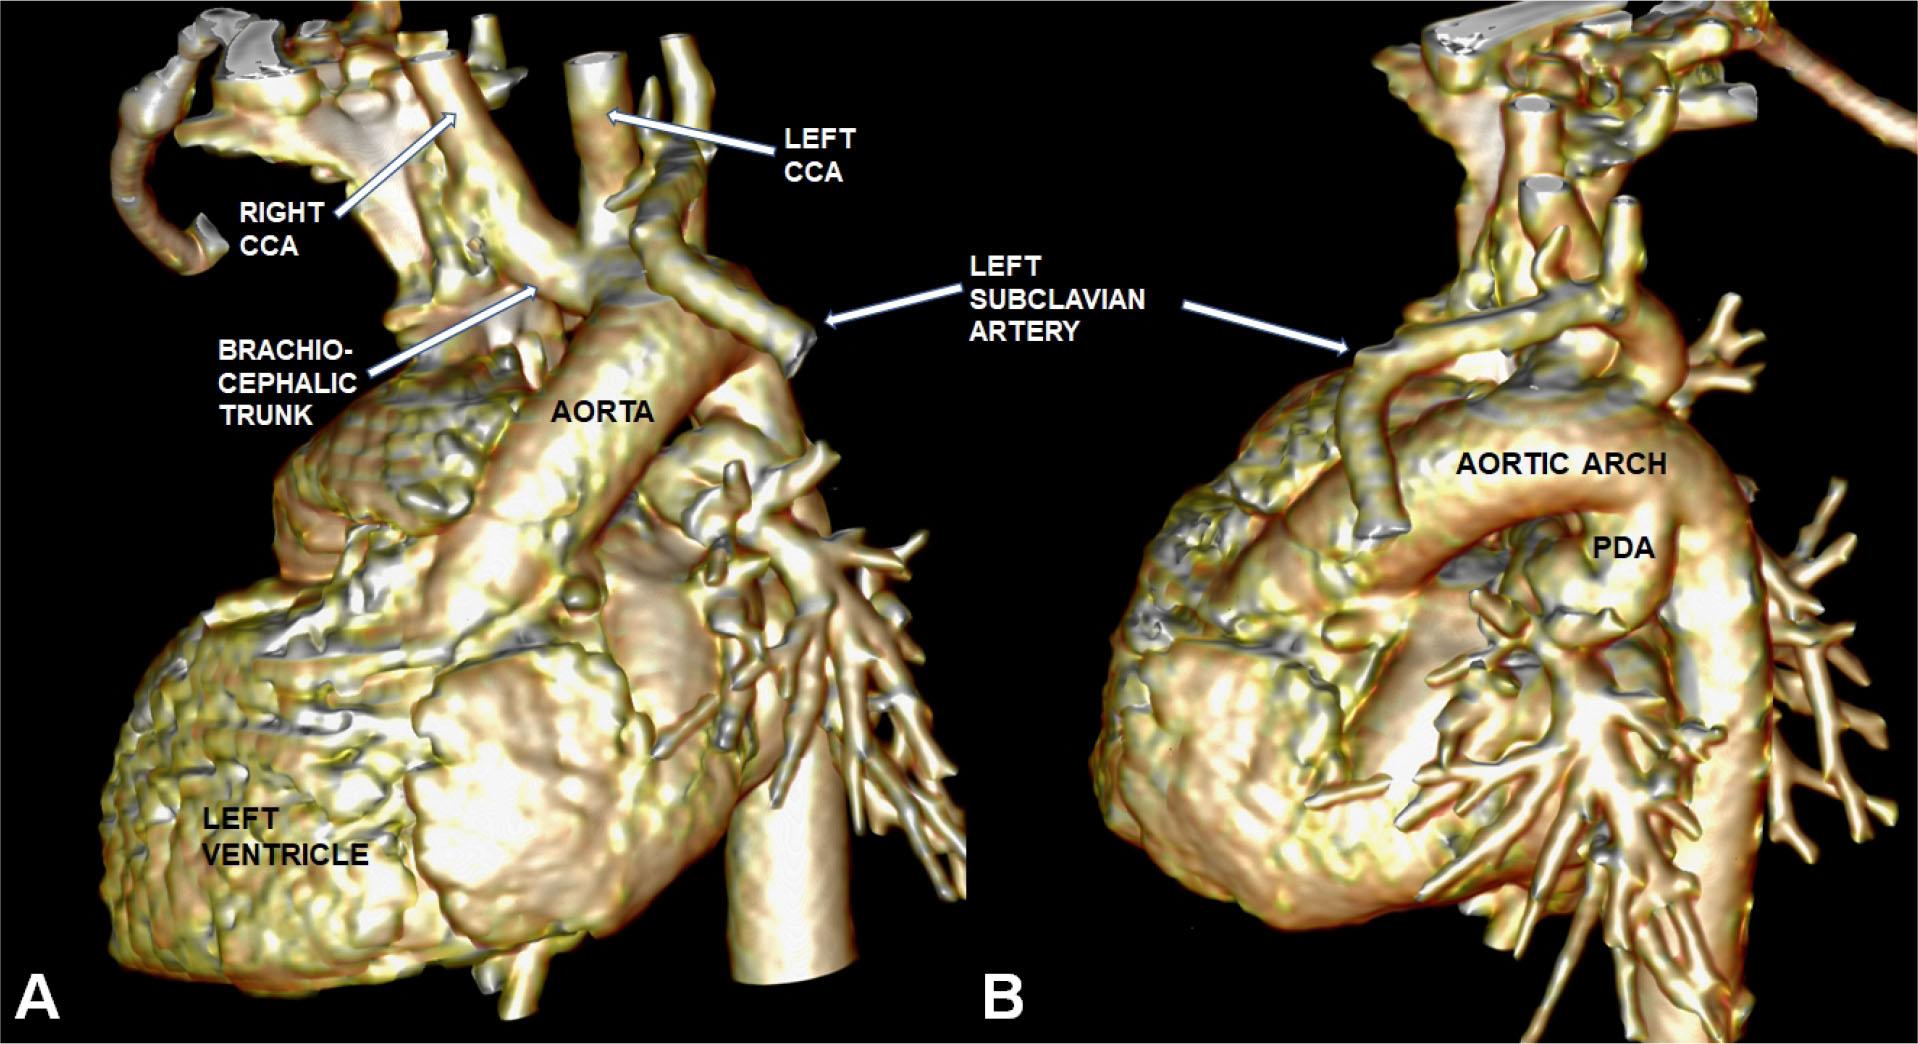

Figure 1